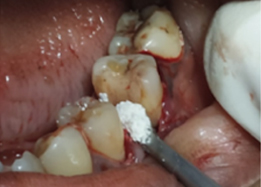

Hemisectomy

Bone Graft Placement

Placement of PRF Membrane